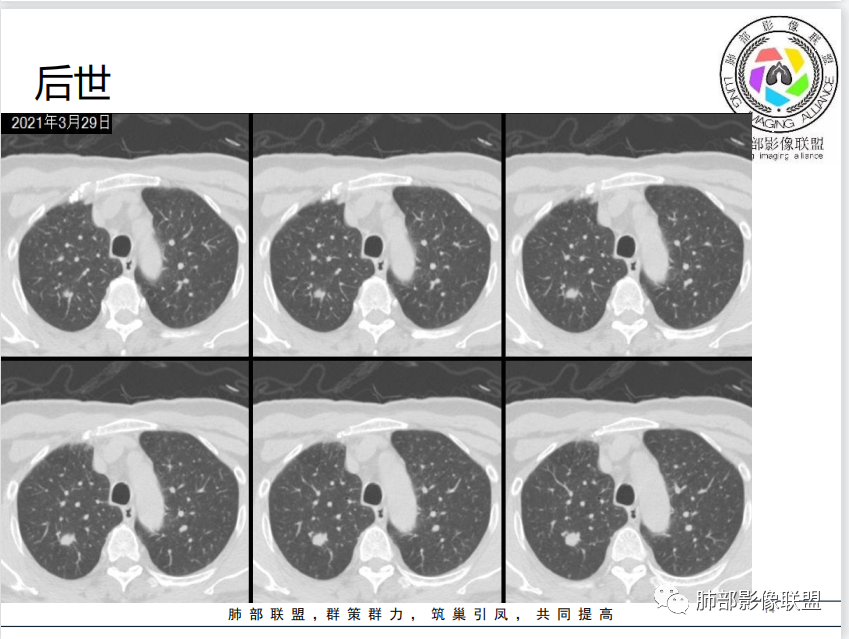

病例资料

病理结果

影像与临床

1、老年男性,4天前受凉后咳嗽、咳痰伴胸痛。

2、既往高血压史、吸烟史。

3、右肺上叶不规则实性密度为主结节影,可见浅分叶,边界隐约可辨,界面欠清晰。病灶密度欠均匀,边缘似可见磨玻璃影,未见钙化及卫星灶。

4、矢状位示病灶沿肺动脉长轴走形,边缘较平直;

5、未提供肺门及纵隔影像。肺门及纵隔淋巴结情况未知。

6、综合分析,右肺上叶单发实性小结节,浅分叶,边界隐约可辨,未能明确与支气管关系。病灶边界不够清晰游离(与邻近肺组织多有瓜葛),加之缺乏周边征象,硬化性肺细胞瘤等良性肿瘤可能性较小。

需要鉴别的是炎性病灶(如炎性肉芽肿)与恶性肿瘤。病灶较小,恶性征象不多(小支气管阻塞、深分叶及毛刺、清楚的磨玻璃晕,张力高等等),仓促定性,未免仓促,可以定期复查是否有变化,穿刺活检也可视为积极措施,唯病灶较小,幽深不测,难度较大。

7.注意:1)血管旁实性密度小结节有时易被“瞒天过海”2)不宜轻视任何一个肺部结节。